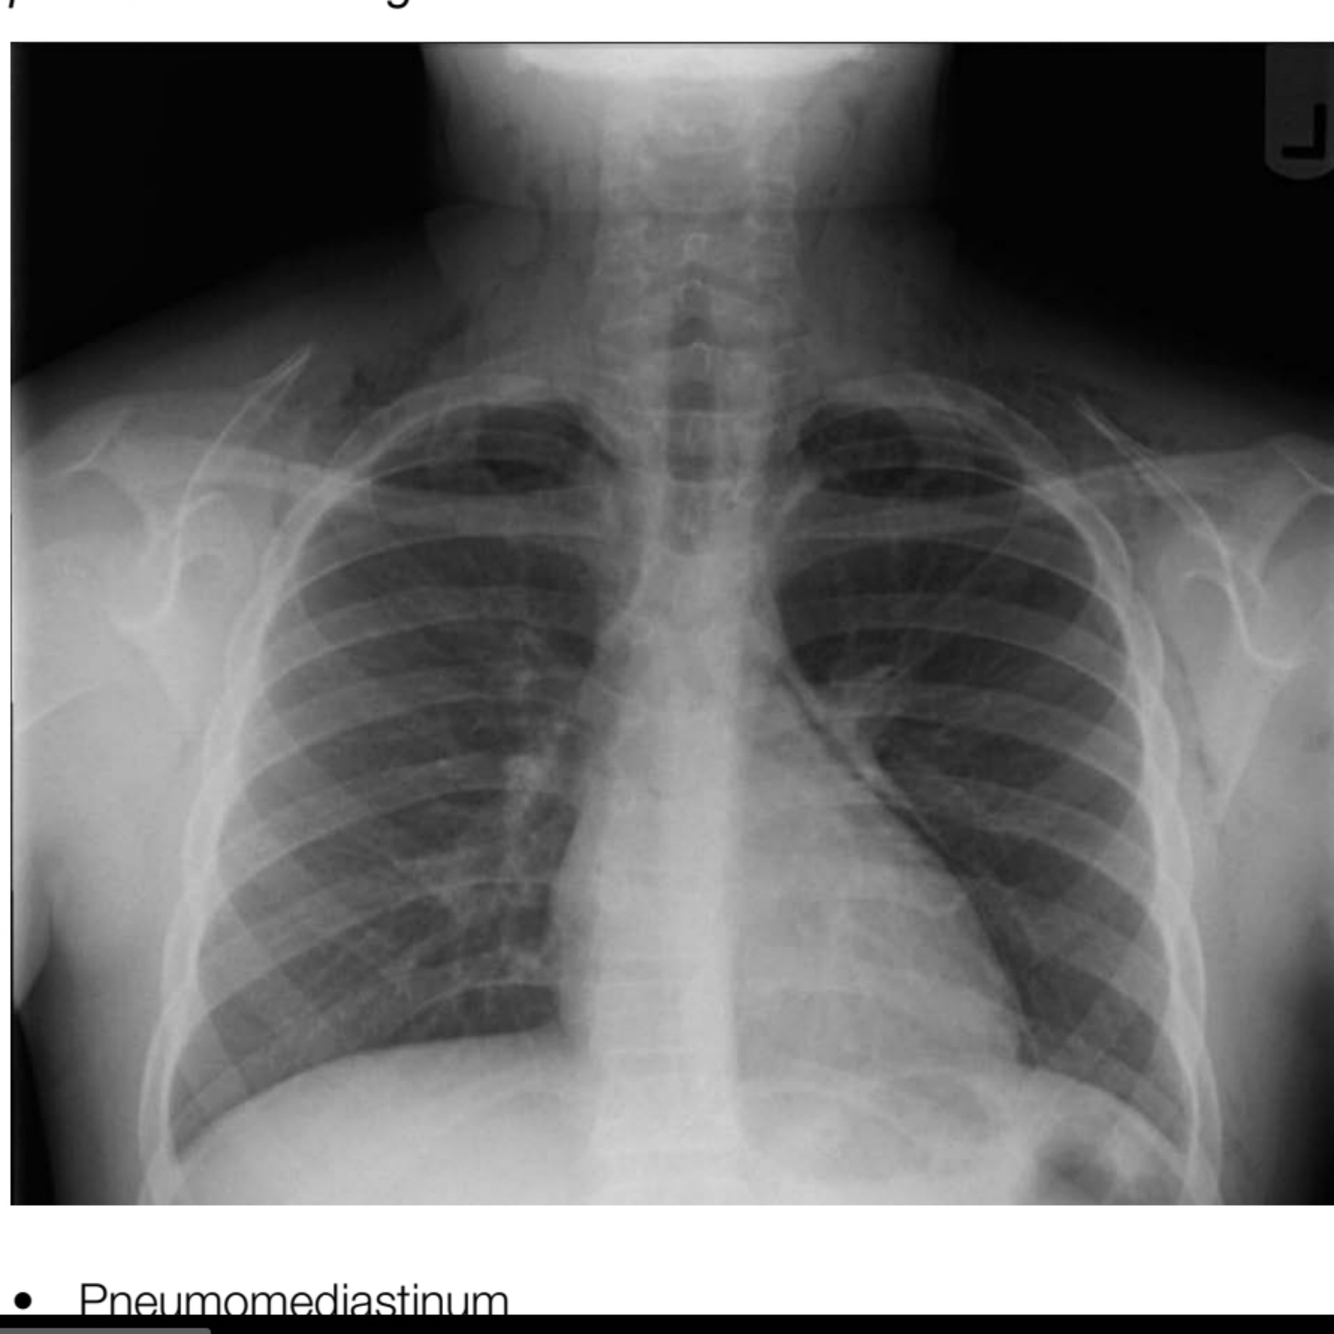

The ICU team has tried to do an early percutaneous tracheostomy, which

was unsuccessful due to technical reasons. An X-ray is done after the

procedure. See Figure 4.1

comment on the chest X-ray

A

• Pneumomediastinum

Cause of pneumomediastinum: Traumatic intubation or tracheostomy/NG

insertion as children have fragile soft tissue in trachea and oesophagus